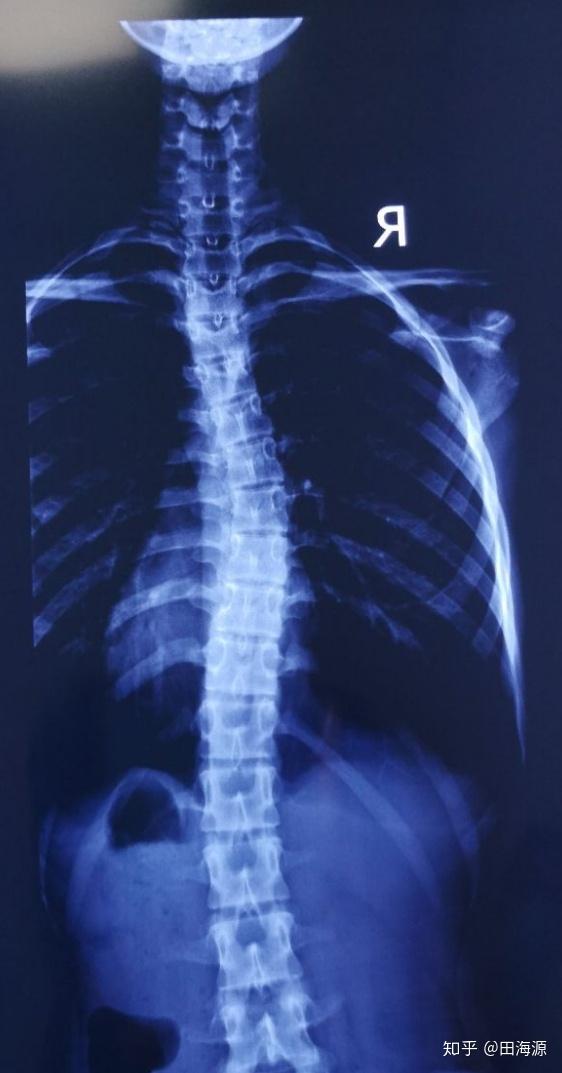

脊柱侧弯曲图片,脊柱侧弯90度照片

男孩脊柱侧弯83度,手术后长高6厘米;专家称若治疗不当

脊柱侧弯

脊柱侧弯90度照片